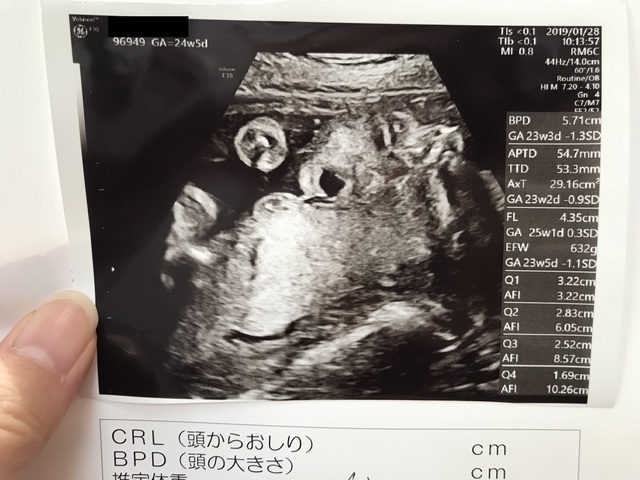

24週0日(24w0d・女の子)|ゆっちゃんちゃん さん(32歳)

エコー写真撮影時のエピソード:

前回の健診では、顔を手で隠していて見せてくれなかったけれど、この健診では顔をはっきり見せてくれてうれしかったです。

またこの次の健診では顔を隠していました。 なかなかはっきり見せてくれるときが少ないです。